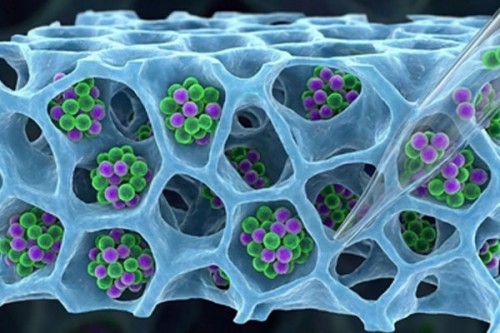

IIT Bombay develops method to recover T-cells for cancer therapies

Technology | IANS | Published : Thu, Feb 05, 2026, 02:59 PM

Japanese researchers to begin human trial for Nipah vaccine in April

Technology | IANS | Published : Wed, Feb 04, 2026, 04:32 PM